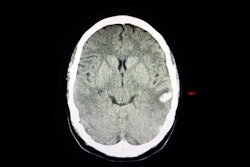

For CT, Gupta said that AI approaches can improve imaging quality and disease prediction. He co-led a study that assessed the performance of a deep learning-based model in predicting intracerebral hemorrhage expansion with dual-energy CT by creating saliency maps. The team found that the convolutional neural network (CNN) model demonstrated promising results. This included an accuracy of 82.7%, 66.7% sensitivity, 75% precision, and 90% specificity.